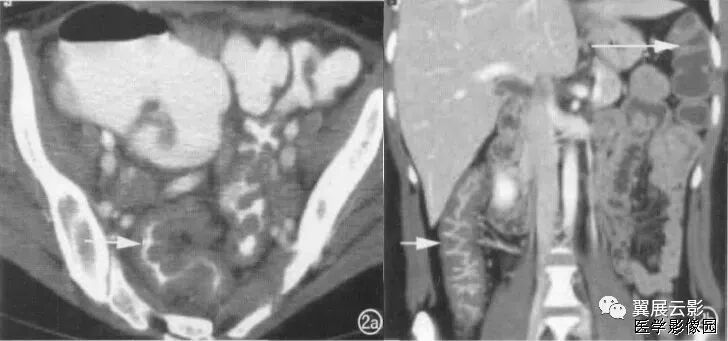

3、不成比例脂肪绞缠征

不成比例脂肪绞缠主要指的是增厚肠壁和周围脂肪在数量方面比例的严重失衡。在少数急性胃肠道疾病中,以肠壁相邻的肠系膜为中心而不是以肠壁为中心,因此肠壁周围脂肪增厚明显高于肠壁厚度。和这一征像相关的疾病主要包括4类:憩室炎、肠脂垂炎、网膜梗死和阑尾炎。胃肠道的大多数炎性疾病包括感染性的、非感染性的和局部缺血性的病变,都是以肠道为中心。这些疾病的肠壁增厚程度往往超过相邻脂肪条索的厚度。但是对于少数以肠壁临近系膜为中心的疾病,脂肪增生明显超过肠壁的厚度。

左上图:右侧腹横肌深面、胆囊内前方梭形囊性病变,有壁但不均匀,略有强化。与腹横肌成锐角,腹横肌肥厚。周围脂肪模糊,有索条点状影。

右上图:邻近降结肠远端系膜壁旁可见一卵圆形类似脂肪密度的病变,周边可见火焰样炎性改变,邻近肠壁有轻微增厚,无明显脓肿及肠梗阻征象。

左下图:肠壁增厚,结肠袋襞显影不良,以及结肠周围脂肪束条状改变。

右下图:CT显示壁明显增强的管状结构(箭头),右中腹的脂肪系膜反应。